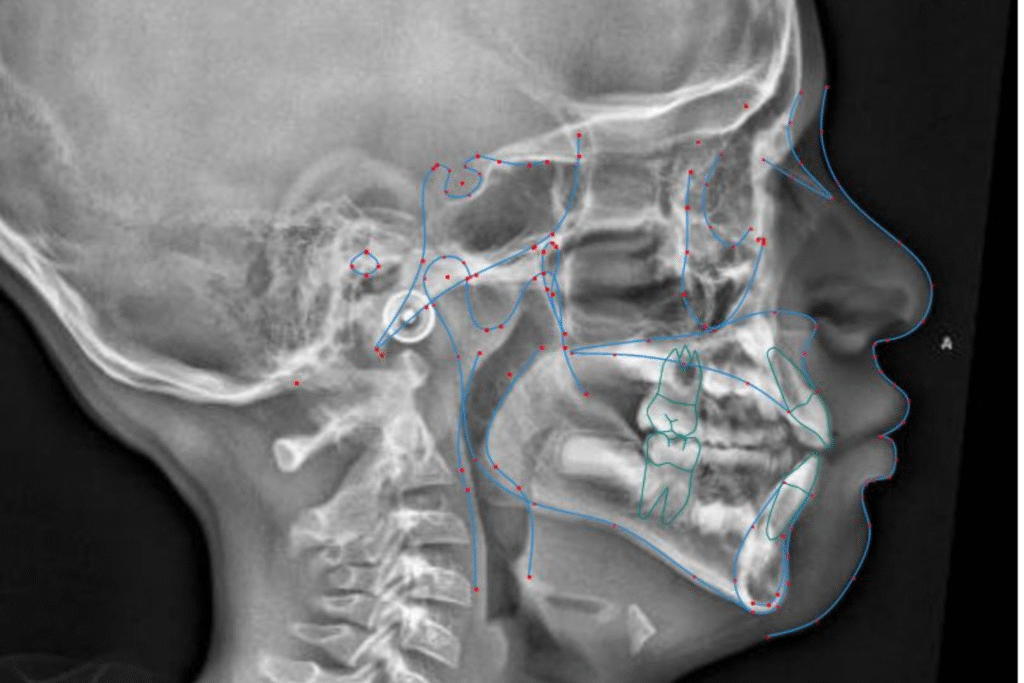

At Bloor West Dental, Health and Wellness, patients are screened for signs and symptoms of sleep disordered breathing (SDB). If indicated, early interventional orthodontics is recommended at different stages depending on individual patient needs. Functional Appliance This treatment is recommended for patients with signs and symptoms of SDB. It is conservative and is usually our…

Craniofacial Growth Guidance is proactive and therapeutic approach in dentistry and orthodontics which monitors and steers the development of a child’s jaw, face and airway into proper alignment during the peak growth years. The treatment intervenes early to address narrow palates, primary crowding, crossbites, receding jaws, breathing issues and signs and symptoms of sleep disordered…